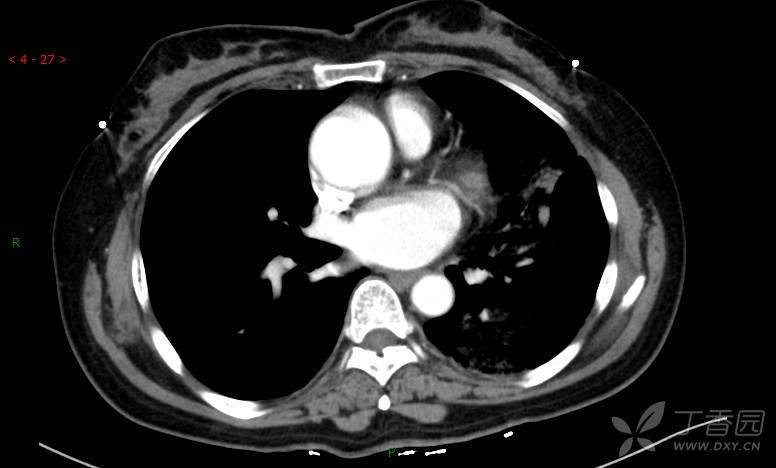

腺泡结节影,蜂窝征,这些都在提示……(病例3连发,附其他2例链接,病理已公布)

咳嗽1年余,加重7天。

患者于1年余前始受凉后出现咳嗽,多为干咳,未在意,未到医院就诊。近3月患者出现咳痰,多为黄色粘痰,量大,伴乏力,偶有头晕、心慌,无发热、胸痛、憋喘,无低热、盗汗、咯血、胸痛,无头痛,无恶心、呕吐、腹痛、腹泻,无尿频、尿急、尿痛,在当地诊所给予抗感染等对症支持治疗(具体药物及剂量不详),症状仍时有反复。患者于1月余前到外院就诊,行胸部CT提示双肺炎症,左肺重,考虑为“间质性肺炎”,给予“左氧氟沙星、利巴韦林、头孢哌酮舒巴坦钠注射液”治疗,复查胸部CT示病灶吸收不理想,后出院继续于诊所对症治疗(具体药物及剂量不详),效果欠佳。7天前患者无明显诱因出现上述症状加重,为求进一步诊治,特来我院就诊,我院门诊以“肺炎(重症)?”收入留观室,留观室给予“盐酸莫西沙星氯化钠”等对症治疗后,今日转入我科。患者自发病以来,神志清,精神差,饮食正常,睡眠增多,大小便正常,体重近3月减轻5公斤余。